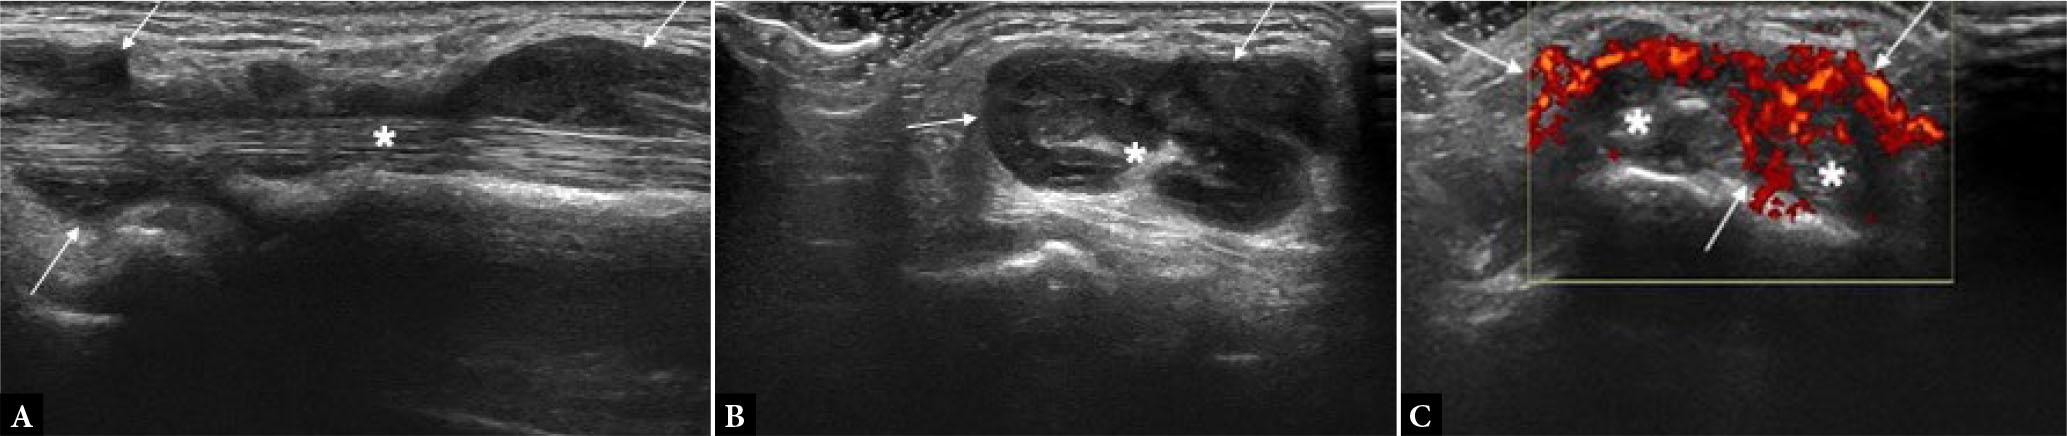

Fig. 15.

Enthesitis. Long-axis US images of Achilles tendon show loss of normal fibrillar echotexture and decreased echogenicity of the tendon insertion (asterisks), punctate calcific foci (small arrow in B), erosions of subentheseal bone (large arrows in A and B) and power Doppler signal at enthesis as seen in B